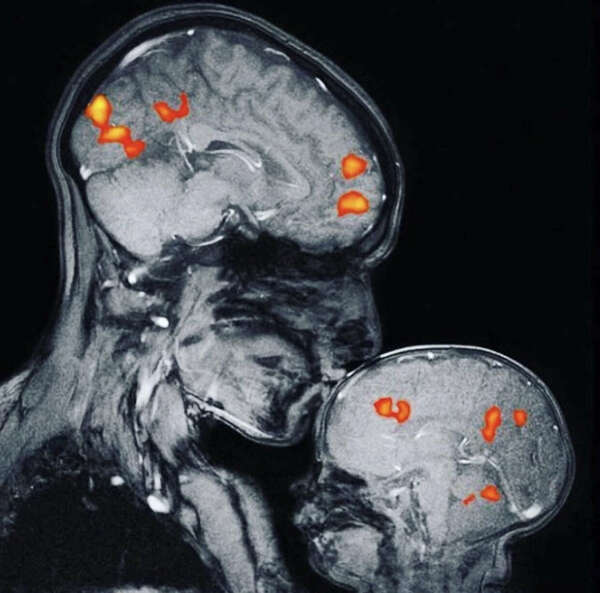

Enfin la preuve en image : Les zones colorées correspondent à la stimulation de l’ocytocine la dopamine, la vasopressine et la sérotonine qui sont les hormon...